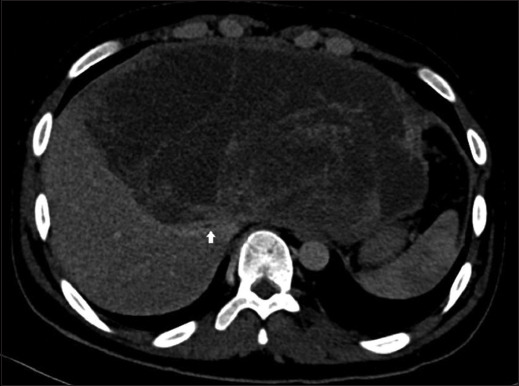

Case description: A 20-year-old boy with a large palpable abdominal mass, shortness of breath, and weight loss presented to our clinic. His computed tomography scan showed showed a large cystic lesion measuring 11.5 × 22.7 × 23 cm, predominantly involving the left lobe and right anterior sector, with a biopsy consistent with UESL. The tumor was abutting to the right hepatic vein, with bland main portal vein thrombosis. Due to an irresectable tumor and deteriorating clinical condition, living donor LT was performed. The patient remains in good health at 16 months of follow-up.